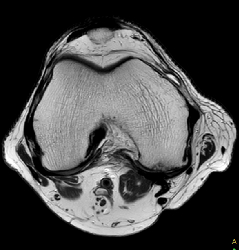

T2w TSE

Ingenia Ambition 1.5T